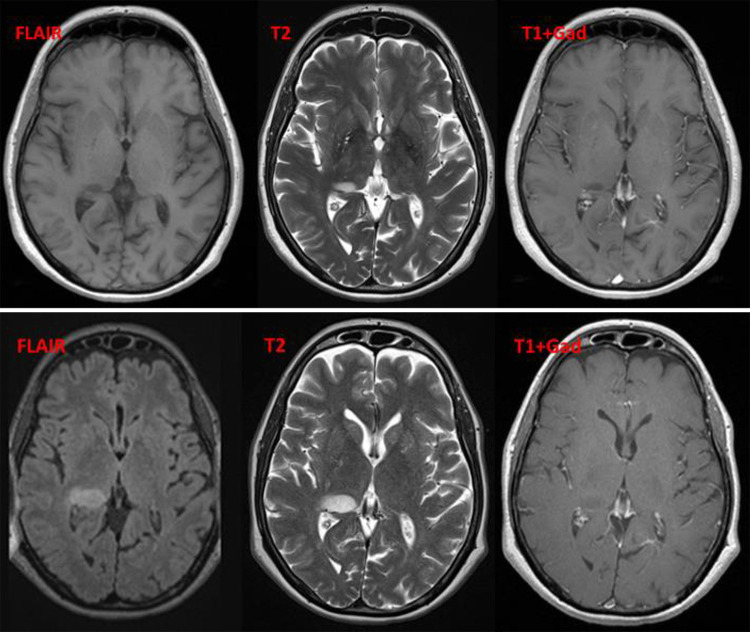

FIG. 3.

Case 2. Upper: Eight years after the initial MS diagnosis, MRI reveals a new small lesion in the right thalamus without enhancement. No perilesional edema can be detected. Lower: Six months later, MRI shows a slight progression in the size of the right thalamic lesions with new enhancement. There is still no perilesional edema. DWI = diffusion-weighted imaging; FLAIR = fluid-attenuated inversion recovery; Gad = gadolinium enhanced; T1 = T1-weighted; T2 = T2-weighted.